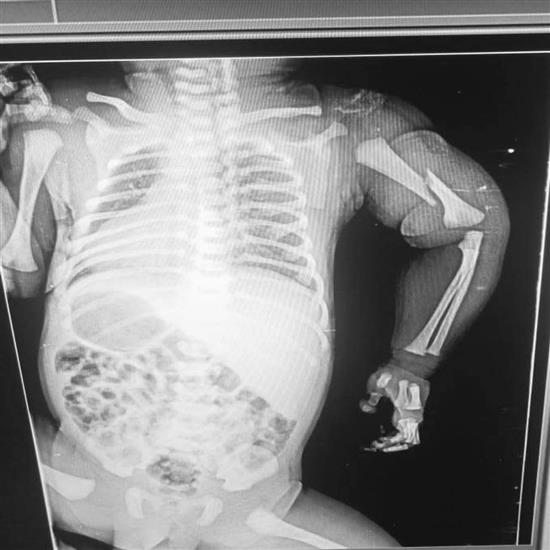

आरोप है कि अस्पताल के डॉक्टर द्वारा बच्चे को पिता से छीनकर जमीन पर फेंक दिया गया, जिससे बच्चे का हाथ टूट गया। जब माता-पिता ने इस अमानवीय व्यवहार का विरोध किया, तो डॉक्टरों की टीम ने उन्हें डराया-धमकाया और कहा कि यदि इस घटना की शिकायत की गई, तो जच्चा और बच्चा सही सलामत नहीं बचेंगे।